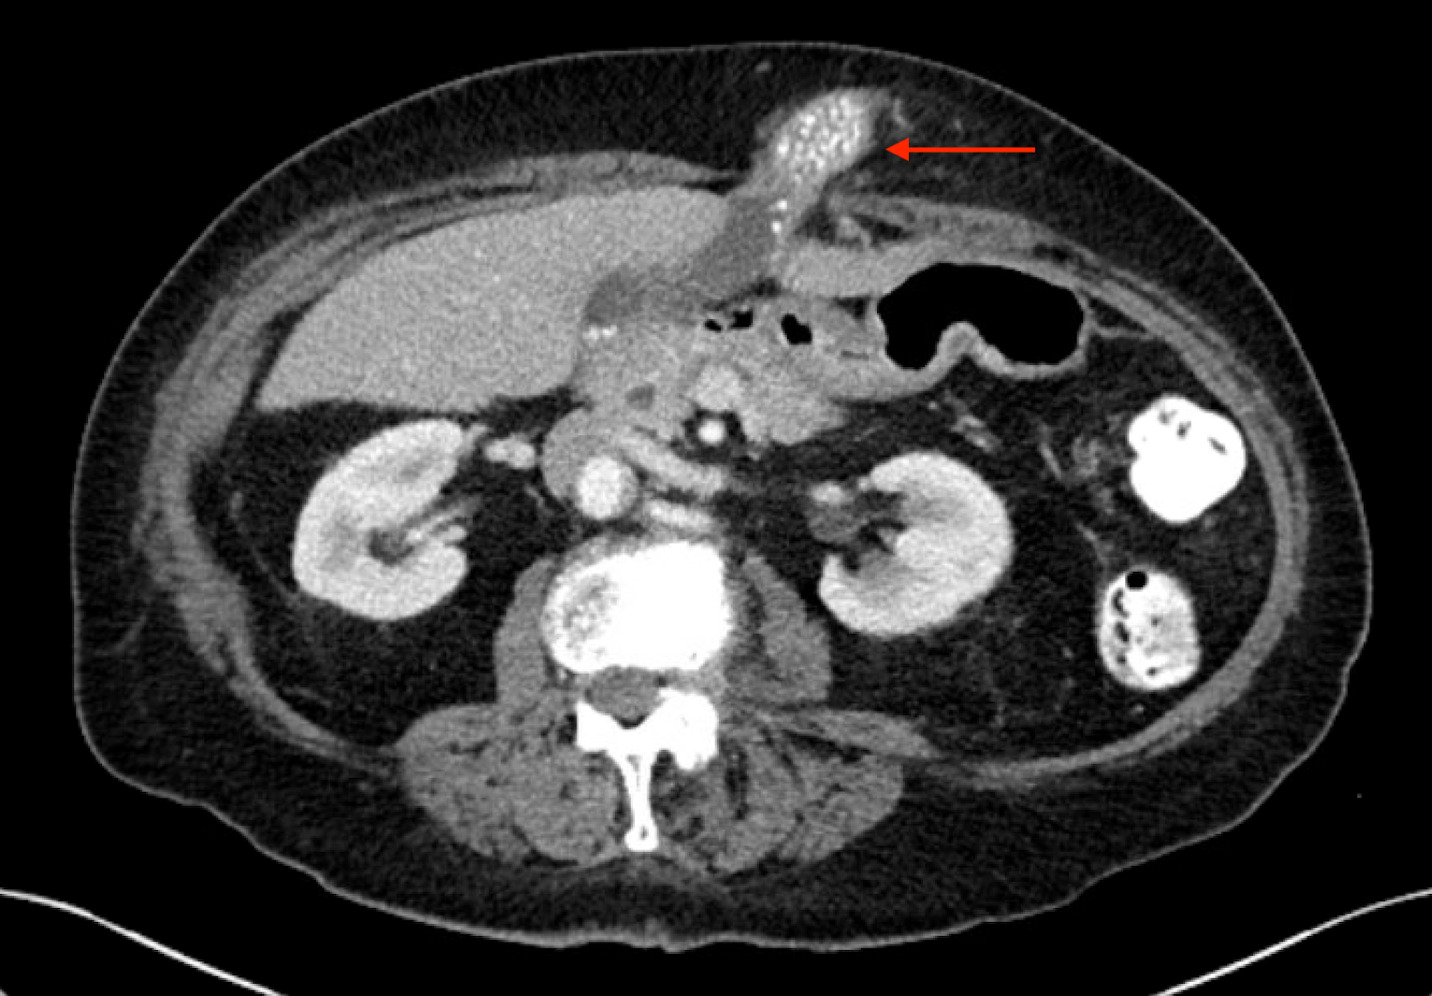

One month prior to her presentation to our outpatient clinic, the patient underwent a CT scan of her abdomen and pelvis with IV and oral contrast. This demonstrated the herniation of a large portion of the gallbladder fundus and body into an epigastric (supraumbilical ventral wall) hernia. The herniated portion contained numerous stones (Figure 1). There appeared to be some mild inflammatory fat changes versus hypervascularity in the abdominal wall surrounding the herniated gallbladder. There was no significant pericholecystic fluid, abscess, or bile duct dilatation. On physical examination, the hernia was found to be firm, non-reducible and moderately tender. Given its state of incarceration and associated symptoms, elective surgery to remove the gallbladder and repair the hernia defect was recommended, and she underwent a peri-operative risk assessment.

A CT scan with IV and oral contrast is the imaging test of choice to diagnose ventral abdominal herniations.5 On CT scan, a gallbladder hernia can be suspected when the gallbladder is absent from its normal anatomical position and a walled structure is present within the hernia that does not contain oral contrast.2 The first step when looking at a ventral hernia on a CT scan is to try to rule out small bowel involvement. For this reason, oral contrast can be useful prior to obtaining the CT scan. Pijpers et al. advocated for MRCP to be used routinely after gallbladder herniation is suspected on a CT scan.7 They stated that this helps rule out gallbladder carcinoma and delineate the tissue planes between the gallbladder and abdominal wall for surgical planning. In our patient, the CT scan clearly demonstrated herniation of an otherwise relatively normal appearing gallbladder, and we felt that no further imaging was necessary as it would not have altered our management.